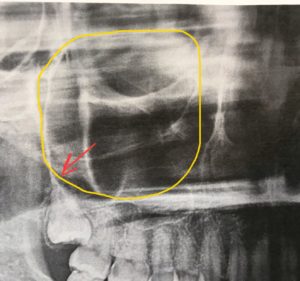

☘️口と上顎洞との関係

続いて上の親知らずの抜歯をした時に起こるリスクについてです。

上の親知らずの根が、生まれながらにして上顎洞という空洞に突出している人がいらっしゃいます。

その場合は抜歯した後、抜歯窩(歯を抜いたあとの穴)と上顎洞が交通し、上顎洞を間にして口と鼻腔がつながってしまいます。

そうなると空気が口から鼻に漏れたり、口から飲んだ水が鼻から出てくることがあります。

穴の大きさによりますが、大部分が自然に閉鎖しますのでご安心ください😊